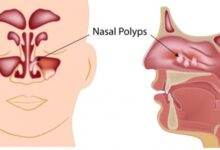

في الحقيقة، يجدُر التوجّه فورًا إلى أخصائي السّمع في الحالات التي يُعاني فيها الشخص من طنين الأذن بما يؤثر في قدرته على سماع الأصوات من حوله، إذ يقوم الأخصائي باتباع إجراءاتٍ وطرق تشخيصية مُعينة تُمكّن من الكشف عن الأسباب الحقيقية التي تكمن وراء المُعاناة من طنين الأذن؛ بما في ذلك الأسباب الجسدية، مع الأخذ بالاعتبار أنّ الأسباب التي تكمن وراء ذلك تتفاوت بدرجاتٍ مُختلفة؛ بدءًا من انسداد قناة الأذن بالشمع وانتهاءً بالإصابة بحالاتٍ مرضيةٍ مُعينةٍ تستدعي الخضوع إلى علاجاتٍ مُحدّدة، وفي هذا السّياق يُشار إلى أنّ تحسين القدرة على سمع الأصوات الحقيقية في البداية يُساهم في تقليل الحاجة لاتباع الطُرق والوسائل المعنية بالتغلّب على مشكلة الطنين، وكذلك الحال فإنّ أخصائي السّمع يلعب دورًا في تحديد الأوقات التي يُعاني الشخص فيها من الطنين ويقوم بتوجيه الأسئلة المعنية بالكشف عمّا إذا كانت شدّة الطنين تزداد سوءًا أثناء الليل، وحول ذلك يُشار إلى أنّ الضجيج وإصدار الأصوات يكون أقل في الليل مُقارنةً بفترات النّهار وبالتالي فإنّ القدرة على إخفاء الطنين المُستمر في الأذنين يكون أقل في الليل، وقد يُوصي الطبيب بالضوضاء البيضاء في سبيل تشتيت الشخص عن صوت الطنين في أذنيه،[١٠] وهُناك العديد من الإرشادات والنّصائح التي يُوصي الأطباء باتباعها في سبيل التخفيف من طنين الأذن، والتي نُبينها فيما يأتي:[١١]